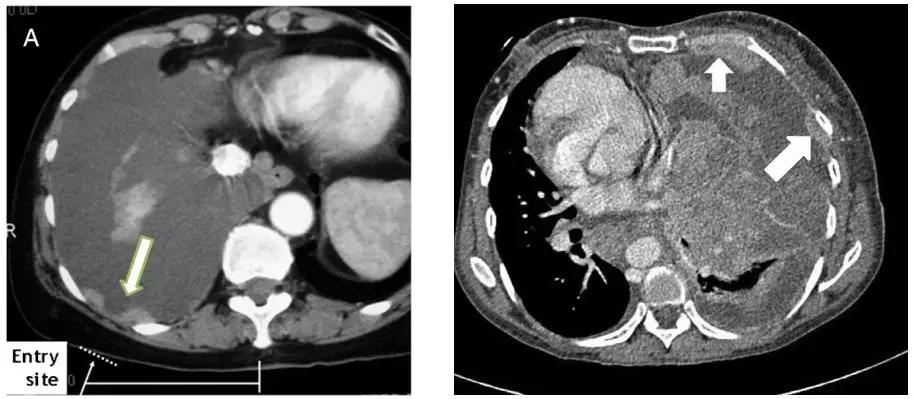

二、CT引导下胸膜活检

优势:精准定位到目标部位,提高诊断敏感性。

如下图,选择增厚、病变比较明显的地方进行穿刺,阳性率较高。

操作步骤比较简单

CT扫描确定胸膜增厚的区域,使用体表定位卡选取最佳进针点,设计好进针方向、深度和角度。穿刺点常规消毒铺巾后,使用同轴套针沿设计好的进针路径缓慢进针,达到计划深度后再次行CT扫描,如确定针尖已达到目标部位后,使用切割针进行穿刺活检。

优势:

①对局灶病变,精确掌握进针点、角度、深度,这些都可以进行调节,比如针进去后,发现没有达到目标部位,可以再进去一点或者拔出来一点;

②能完成特殊部位(肩胛骨/纵隔附近)的活检。

男性,68岁,CT示:左下肺后基底段结节影伴左侧胸膜局灶性增厚。CT引导下胸膜穿刺活检证实为腺癌。

CT引导下胸膜活检的敏感性和特异性相对较高,对患者有利。